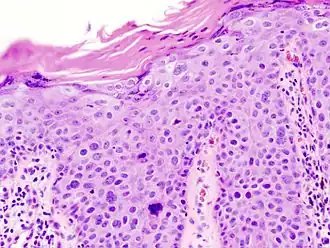

Histological characteristics

Histopathologically, the epidermis in cSCC in situ (Bowen's disease) will show hyperkeratosis and parakeratosis. There will also be marked acanthosis with elongation and thickening of the rete ridges. These changes will overly keratinocytic cells, which are often highly atypical and may have a more unusual appearance than invasive cSCC. The atypia spans the full thickness of the epidermis, with the keratinocytes demonstrating intense mitotic activity, pleomorphism, and greatly enlarged nuclei. They will also show a loss of maturity and polarity, giving the epidermis a disordered or "windblown" appearance.

Two types of multinucleated cells may be seen: the first will present as a multinucleated giant cell, and the second will appear as a dyskeratotic cell engulfed in the cytoplasm of a keratinocyte. Occasionally, cells of the upper epidermis will undergo vacuolization, demonstrating an abundant and strongly eosinophilic cytoplasm. There may be a mild to moderate lymphohistiocytic infiltrate detected in the upper dermis.[12]

Histopathology of squamous-cell carcinoma in situ (black arrow), compared to normal skin, showing marked atypia. -

Squamous-cell carcinoma in situ, showing prominent dyskeratosis and aberrant mitoses at all levels of the epidermis, along with marked parakeratosis.[12]